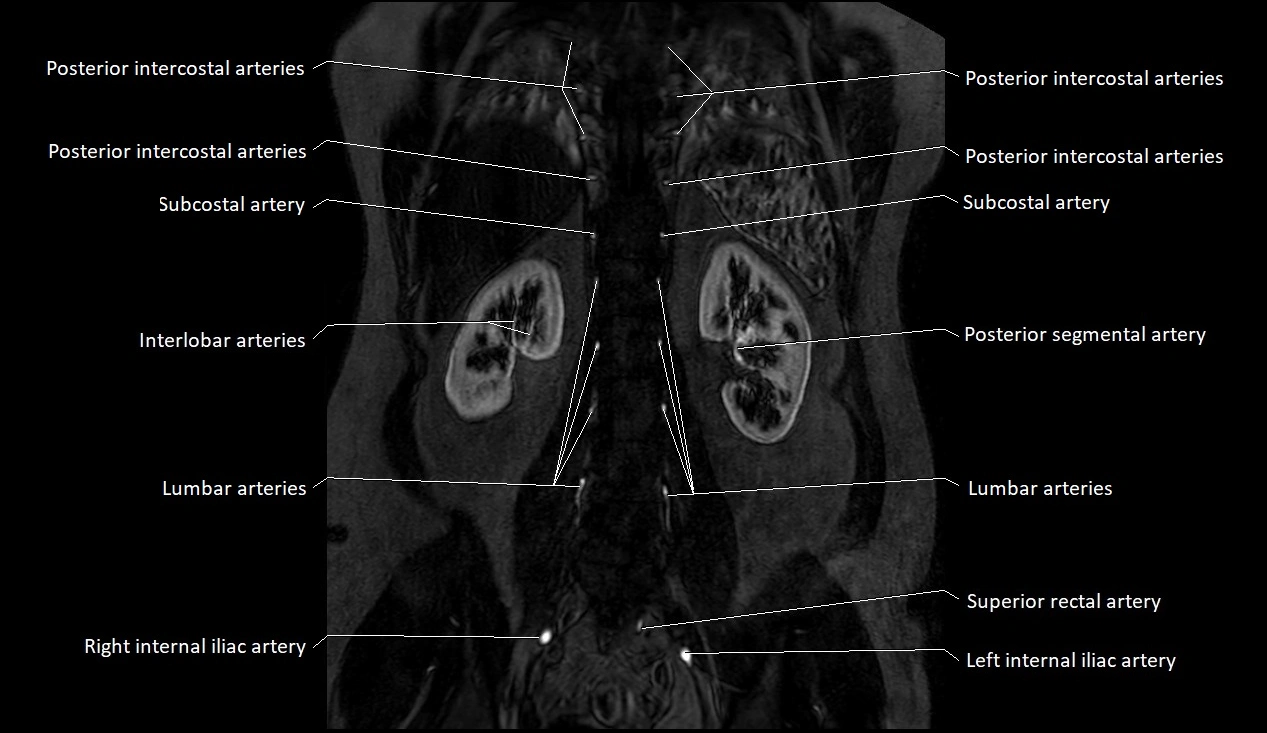

MRI images

image